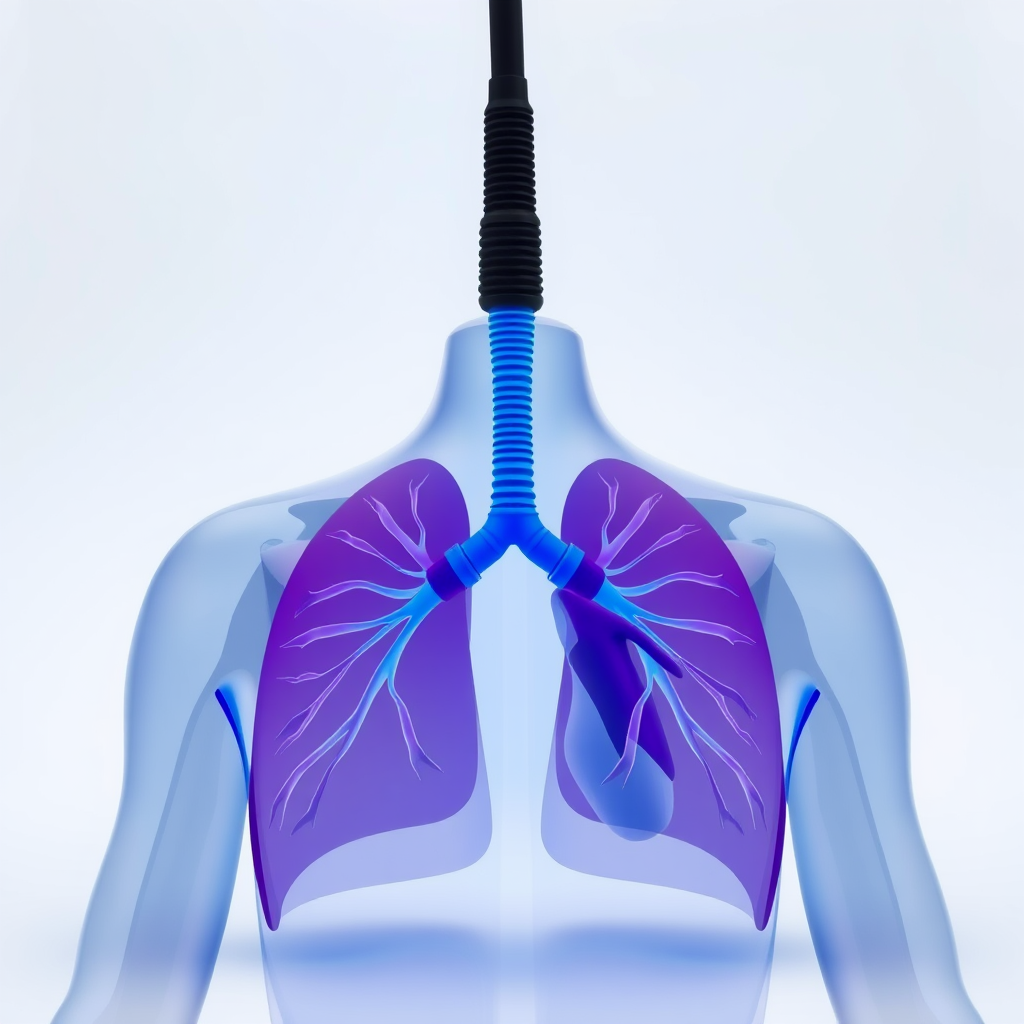

Melhora da saúde cardiovascular

Um dos principais objetivos da clínica de reabilitação cardíaca é a melhora da saúde do coração.

Isso ocorre por meio de programas de exercícios supervisionados e monitoramento constante.

Aumento da qualidade de vida

A clínica de reabilitação cardíaca também contribui para a qualidade de vida.

Além da melhora física, há impacto positivo no bem-estar geral.

Redução de sintomas como fadiga e falta de ar.

Redução do risco de novos eventos cardíacos

Outro benefício importante da clínica de reabilitação cardíaca é a redução do risco de recorrência.